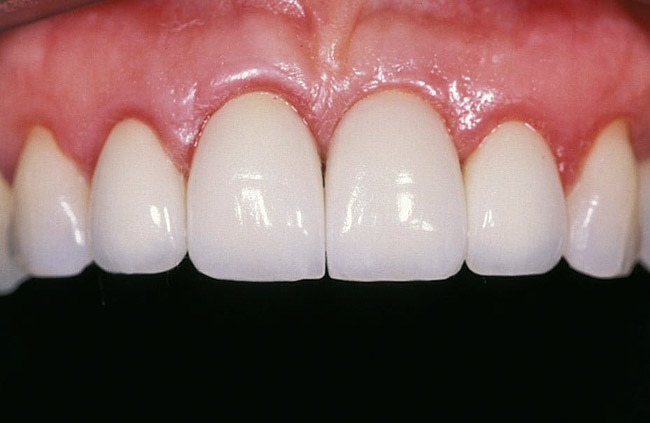

Fig 14. The final restoration will produce the results the patient should expect from the treatment planning discussions and provisional development.

Figure 14